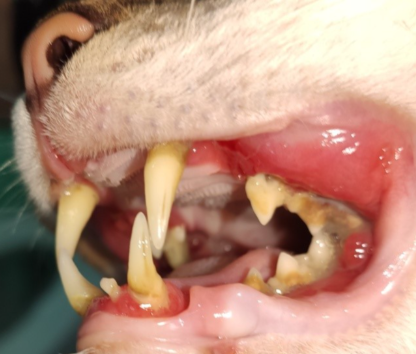

-Odontología: Gingivoestomatitis crónica felina (foto), Reabsorción dental…